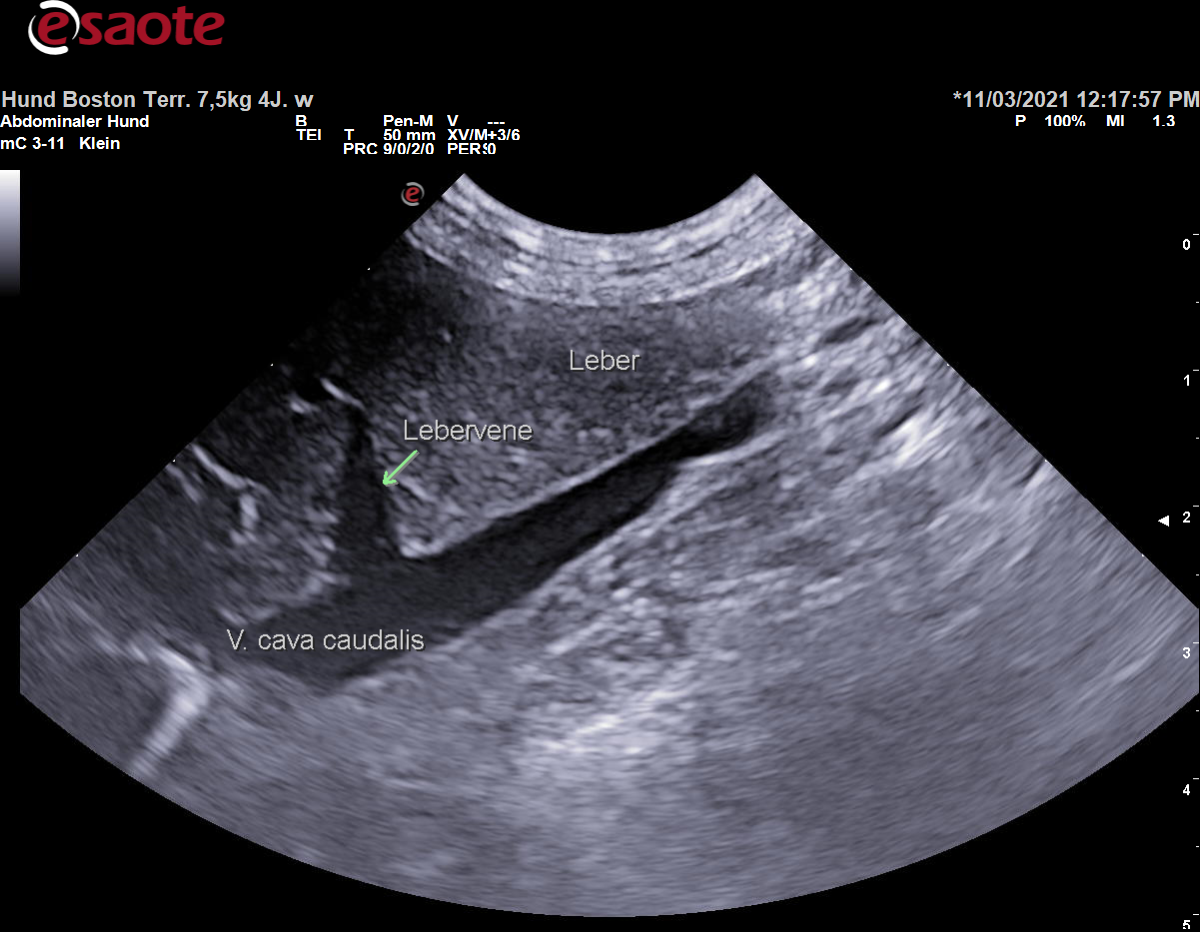

- Vv. hepaticae:

Bei ihrem Verlauf über die Facies diaphragmatica der Leber entspringen der V. cava caudalis die Vv. hepaticae sinistra, media und dextra für die verschiedenen Leberlappen, sowie beim Hund die V. hepatica accessoria.